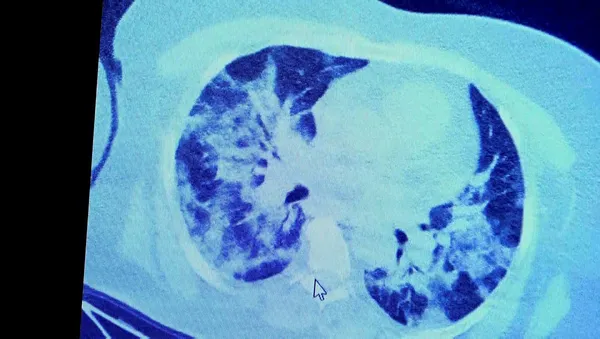

Tomografide akciğerlerdeki tutulmanın az olduğu gözlemlendi. Akabinde aynı hastanın verilen ilaçları kullanmamış ve 1 hafta boyunca tedaviye uymamış haldeki akciğer tomografisine bakıldı. Sonuç ise ilaç kullanımının önemini ortaya çıkardı. Hastanın akciğer tomografisinde yaygın buzlu camların ve hava yollarının hava yerine ciddi şekilde sıvı ile dolduğu gözlemlendi.

Akciğer tomografisinde oluşan değişim ile ilgili bilgi veren Prof. Dr. Şevket Özkaya, "Ekranda 55 yaşında bir kadın hastamızın filmini görüyorsunuz. Bu kadın hastamız acil servisimize ateş şikâyetiyle geldi ve korona virüsünden şüphe ettik. Testini yaptığımızda ise testin sonucu pozitif geldi. Tomografi çektiğimiz zaman akciğerlerinde henüz ciddi bir tutulum görünmezken hastamız 55 yaşında olduğu için her an ilerleyebilir korkusuyla Sağlık Bakanlığımızın önerdiği ilaçları ve reçeteyi hastanemizden kendisine verdik. Hasta kendini evde karantinaya aldı fakat sonradan öğrendik ki tereddüt ettiği için ilaçlarını kullanmayarak kendini evde tedavisiz bırakmış. Yaklaşık bir hafta sonra aynı hasta acil servisimize bu sefer solunum yetmezliği şikâyetiyle geldi. Solunum yetmezliği gelişince hastanın akciğer tomografisinde 'buzlu cam' dediğimiz ve daha ileri konsolide alanların oluştuğunu gördük. Yaygın akciğer harabiyeti dediğimiz bir tablo oluşmuştu. Bu durumda hastada solunum yetmezliği olduğu için yoğun bakıma almak zorunda kaldık" dedi.